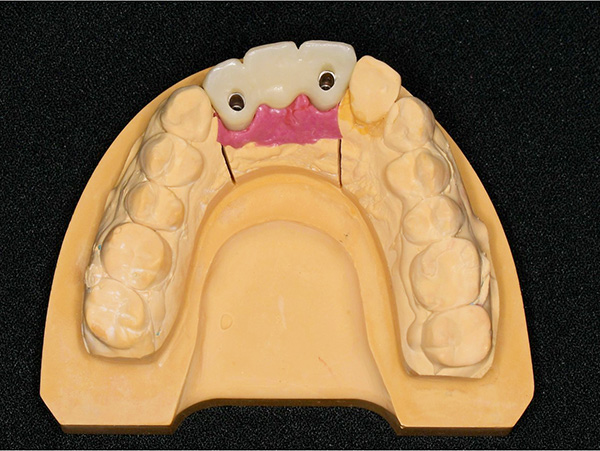

上部構造物

(ジルコニアボンドブリッジ)

スクリューリテイン(ねじ止めタイプ)による上部構造物を製作しました。

ジルコニアボンドはジルコニアのフレームの上にセラミックを盛り付けています。

インプラント体との連結部分以外に金属を一切使用していませんので、審美性に優れていますが、

セラミック部分がかける可能性があります。

上部構造物装着

上部構造物を装着した状態です。まだ装着して日が浅いので、今後歯ぐきとの馴染みが十分ではありません。 インプラントは虫歯にはなりませんが、インプラント周囲炎になる可能性がありますので、今後は定期検診で確認し、健康な状態を維持していくよう努めていきます。